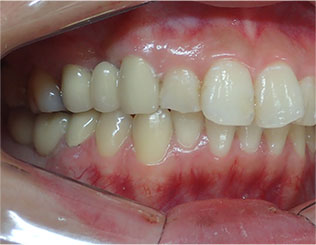

- ブリッジ 症例写真 B-0113FZC8本 女性モニターの方です。

この方は古い差し歯の黄ばみを治したいとご来院されました。 奥歯に欠損もありましたので、前歯はジルコニアセラミック、奥はジルコニアブリッジで治しました。 1回の治療で前歯も奥歯も同時進行で治療します。 1回目の治療時に仮歯を入れますので、すぐに見た目が気にならなくなります。 治療回数は5回でした。